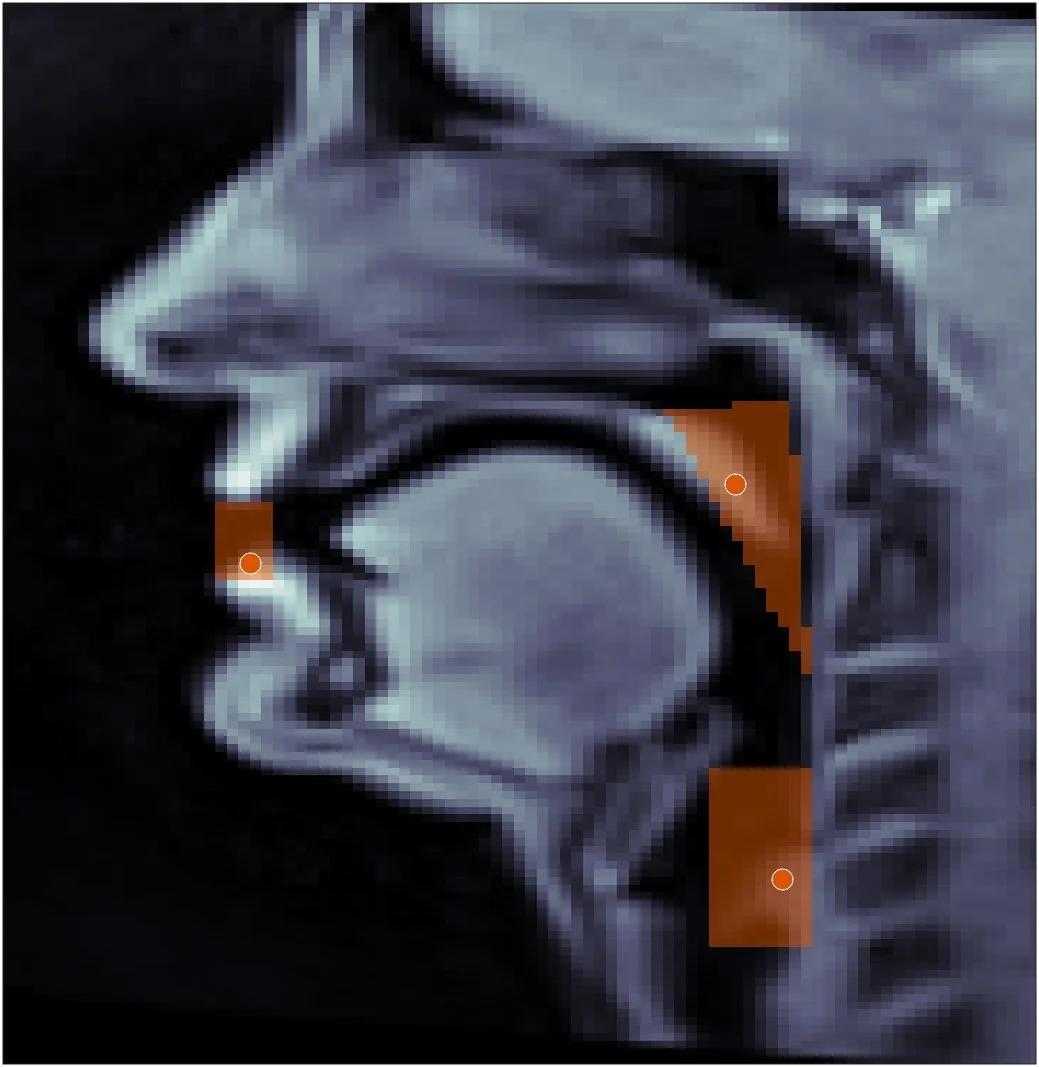

A modular pipeline for processing rtMRI speech data, supporting pixel-wise standard deviation mapping, interactive ROI drawing, frame-by-frame articulator tracking via intensity-weighted centroids, and velopharyngeal aperture estimation. Synchronized MRI/audio visualization and video export are also provided.